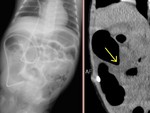

[画像診断]尿管癌のT因子について 【研修医と学ぶ】 2010-08-04